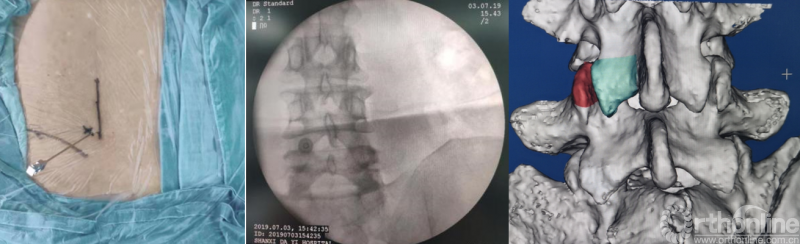

第一步“定”:X线定位在上位椎体下关节突下三分之一部;

第二步“辨”:镜下辨别下关节突关节囊;

第三步“凿”:凿除部分下关节突,显露上关节突及黄韧带;

第四步“分”:分离上关节突及黄韧带;